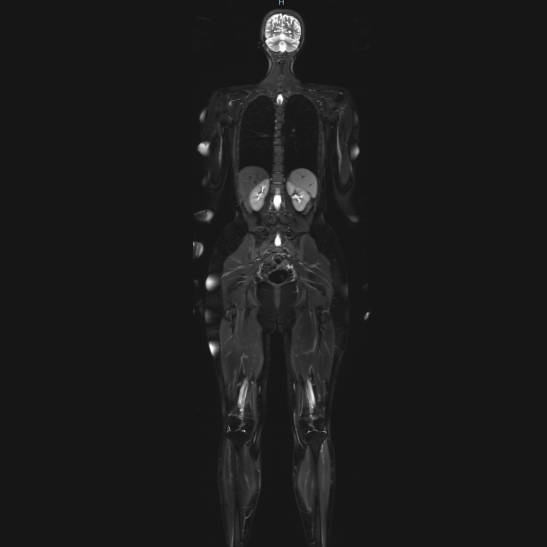

Unsere umfangreichen Möglichkeiten zur Früherkennung umfassen unter anderem die Ganzkörper-Magnetresonanztomografie (MRT). Mit diesem Verfahren können wir Ihren gesamten Körper in hoher Detailgenauigkeit darstellen und eventuelle Anomalien oder Auffälligkeiten frühzeitig identifizieren.

Darüber hinaus können zusätzlich zur Ganzkörperuntersuchung detaillierte Darstellungen von einzelnen Körperregionen, wie der Prostata oder das Herz indiziert sein. So ist es uns möglich, Veränderungen frühzeitig zu erkennen, was bei der Prävention von entscheidender Bedeutung ist.